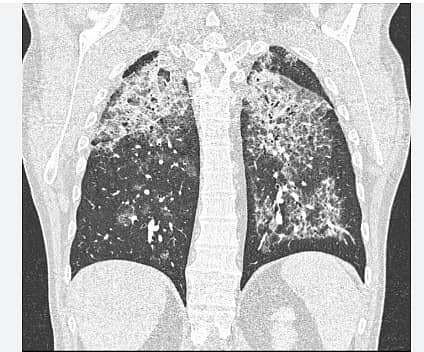

ಈ ಕುರಿತು ಮಾತನಾಡಿದ ಡಾ. ವಿವೇಕ್ ಗುಂಡಪ್ಪ, ಉಸಿರಾಟದ ಸಮಸ್ಯೆಗಳು ಗಂಭೀರವಾದಾಗ ಮೊದಲು ನಿಮೋನಿಯಾ ಇರಬಹುದು ಎಂದೇ ಭಾವಿಸಲಾಗುತ್ತದೆ. ಇದೇ ರೀತಿಯ ರೋಗಲಕ್ಷಣಗಳಾದ ದೀರ್ಘಾವಧಿ ಕಫ, ಉಸಿರಾಟ ಸಮಸ್ಯೆ, ನಿರಂತರ ಆಯಾಸದಿಂದ ಬಳಲುತ್ತಿದ್ದ 39 ವರ್ಷದ ಮಹಿಳೆಗೆ ಮೊದಲು ವೈರಲ್ ನಿಮೋನಿಯಾ ಸೋಂಕಿನ ರೋಗ ಪತ್ತೆ ಮಾಡಲಾಗಿತ್ತು, ಹಲವು ಸುತ್ತಿನ ವೈದ್ಯಕೀಯ ಚಿಕಿತ್ಸೆಯನ್ನೂ ನೀಡಲಾಗಿತ್ತು. ಆದರೆ ದೇಹದ ಸ್ಥಿತಿ ದಿನೇ ದಿನೇ ವಿಷಮಿಸುತ್ತಿದ್ದುದರಿಂದ, ವೈದ್ಯರ ತಂಡ ಎಚ್ಚೆತ್ತುಕೊಂಡು, ಎದೆ ಭಾಗದ ಎಕ್ಸ್ ರೇ ತೆಗೆದಾಗ ಅತ್ಯಂತ ವಿರಳವಾದ ಚಿತ್ರ ಕಂಡಿತು, ಅಷ್ಟೆಅಲ್ಲದೆ, ಸಿಟಿ ಸ್ಕ್ಯಾನ್ ಮಾಡಿದಾಗ ಇದು ನಿಮೋನಿಯಾ ಅಲ್ಲವೆಂಬುದು ವೈದ್ಯರಿಗೆ ಖಾತ್ರಿ ಆಗಿತ್ತು.

ಶ್ವಾಸಕೋಶದ ಚಿತ್ರಣ ಪತ್ತೆಗೆ ಬ್ರಾಂಕೋಸ್ಕೋಪಿ ನಡೆಸಿದಾಗ ಶ್ವಾಸಕೋಶದಲ್ಲಿನ ದ್ರವ ಹಾಲಿನ ರೂಪದಲ್ಲಿದ್ದುದು ಕಂಡು ಬಂದಿತ್ತು. ಇನ್ನೂ ಹೆಚ್ಚಿನ ವಿಶ್ಲೇಷಣೆ ನಡೆಸಿದಾಗ ಪಲ್ಮನರಿ ಅಲ್ವಿಯೋಲಾರ್ ಪ್ರೊಟಿನೋಸಿಸ್ (ಪಿಎಪಿ)ಎಂಬುದು ಖಾತರಿ ಆಗಿತ್ತು.